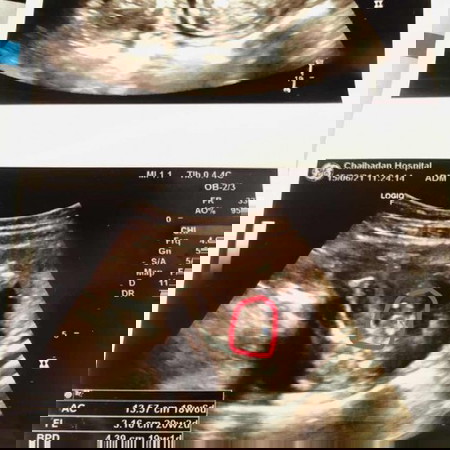

แม่ๆช่วยดูหน่อยค่ะ

แบบนี้ เพศอะไรคะ

ชายค่ะ